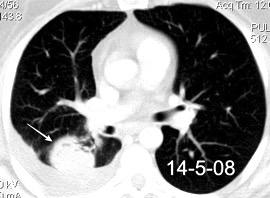

Nefrectomia derecha en 1996 por adenocarcinoma renal. Reseccion de metastasis pulmonar en LSI de carcinoma renal. Sospecha de nueva metástasis.

Granuloma de cuerpo extrano por hilo de sutura en situación cisural